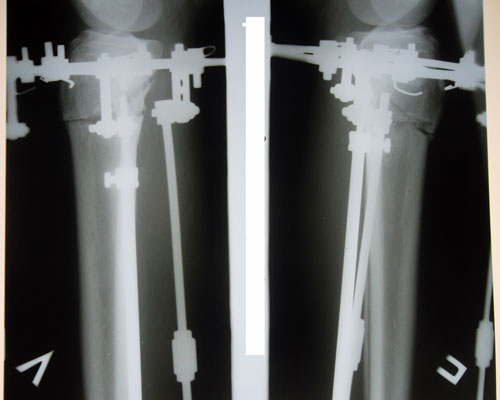

Дата операции 14.01.2014г.

Дата снятия аппаратов 15.04.2014г.

Срок лечения 3 месяца.